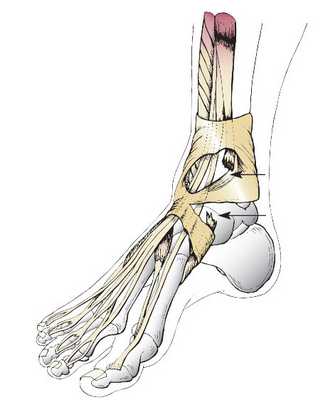

Предложенный способ иллюстрируется графическим материалом. На рис. 1 показаны Рис. 1. Выделение короткой малоберцовой и задней большеберцовых мышц. 1 — проксимальный конец ахиллова сухожилия; 2 — дистальный конец ахиллова сухожилия; 3 — сухожилия короткой малоберцовой мышцы; 4 — малоберцовая мышца; 5 — сухожилия задней большеберцовой мышцы; 6 — задняя большеберцовая мышца. проксимальный конец (1) и дистальный конец (2) ахиллова сухожилия. Выделено и взято на держалку сухожилие (3) короткой малоберцовой мышцы (4). Выделено и взято на держалку сухожилие (5) задней большеберцовой мышцы (6).

На рис. 2: Рис. 2. Перемещение и пластика дефекта ахиллова сухожилия. 1 — проксимальный конец ахиллова сухожилия; 2 — дистальный конец ахиллова сухожилия; 3 — сухожилия короткой малоберцовой мышцы; 4 — малоберцовая мышца; 5 — сухожилия задней большеберцовой мышцы; 6 — задняя большеберцовая мышца; 7 — швы, фиксирующие концы ахиллова сухожилия. сухожилие (3) короткой малоберцовой мышцы (4) и сухожилие (5) задней большеберцовой мышцы (6) проведены через трехглавую мышцу, перекрывают дефект между проксимальным концом (1) и дистальным концом (2) ахиллова сухожилия, натянуты до оптимального натяжения и фиксированы швами (7) параллельно друг другу к дистальному концу (2) ахиллова сухожилия.